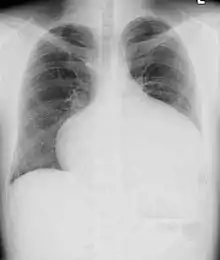

Adults with an uncorrected ASD present with symptoms of dyspnea on exertion (shortness of breath with minimal exercise), congestive heart failure, or cerebrovascular accident (stroke). They may be noted on routine testing to have an abnormal chest X-ray or an abnormal ECG and may have atrial fibrillation. If the ASD causes a left-to-right shunt, the pulmonary vasculature in both lungs may appear dilated on chest X-ray, due to the increase in pulmonary blood flow.[32]